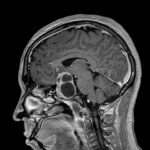

La exploración física es una herramienta fundamental que utilizan los médicos y otros profesionales de la salud para evaluar la salud de una persona y detectar posibles enfermedades. Esta técnica se basa en el examen físico del paciente, que incluye la observación, palpación, percusión y auscultación de los diferentes sistemas del cuerpo.

El objetivo principal de la exploración física es identificar los signos físicos de la enfermedad. Los signos físicos son cambios objetivos en el cuerpo que pueden ser observados o medidos y que indican la presencia de una enfermedad. Estos signos pueden incluir cambios en la piel, como erupciones o lesiones, cambios en la respiración, como la presencia de ruidos anormales, y cambios en la función de los órganos, como la disminución de la función renal o hepática.